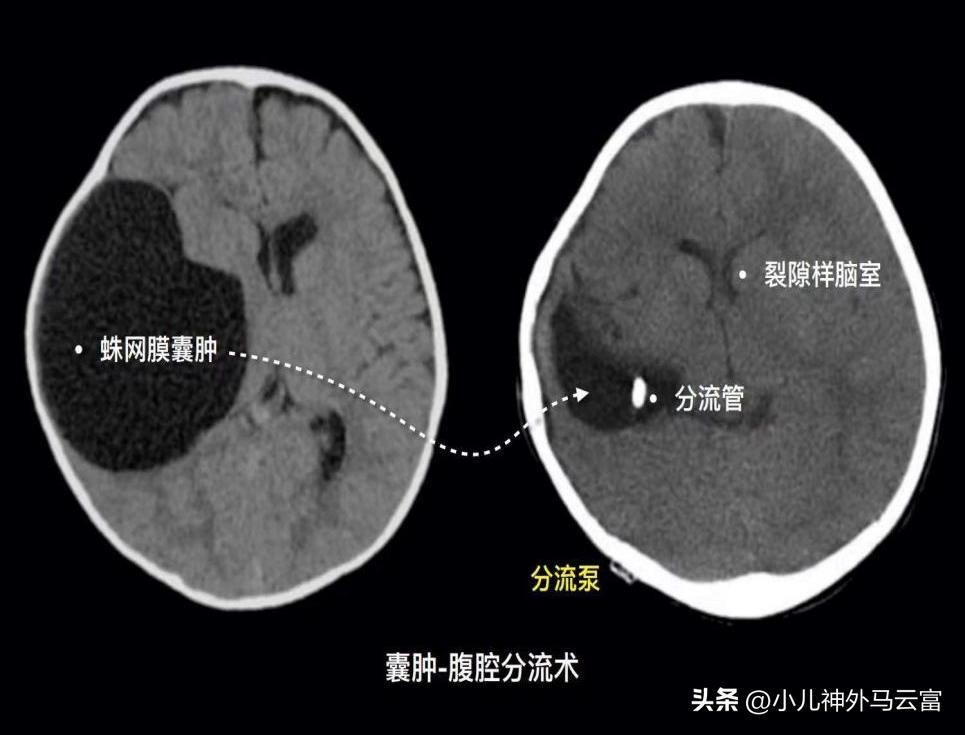

(3)囊腫-腹腔分流術

對有症狀者,應慎重選擇手術方式,囊腫-腹腔分流手術雖然具有最好的囊腫縮小率及消失率且具有簡單、高效、併發症少的優點,但必須要正視其潛在分流管依賴的高風險;